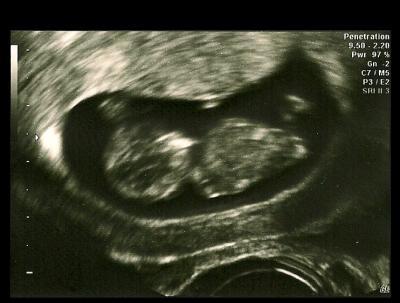

Hallo zusammen, ich bin gestern nicht mehr dazu gekommen, deshalb hole ich heute meinen FA-Bericht nach. Ich war ja gestern in SSW 10+1. SSL war 3,5 cm, was lt. US-Gerät 10+3 entspricht. Der ET wird aber wahscheinlich nicht geändert. Ich glaube, mein FA macht das erst ab 7 Tagen Differenz, wenn ich mich recht entsinne. Wie ist das bei euch mit der ET-Korrektur? Der nächste Termin ist nun schon die NT-Messung am 27.9. Ich habe mich jetzt entschieden, sie bei meinem FA zu machen (war mir ja noch nicht sicher). Blöderweise ist am Donnerstag drauf der Feiertag und am Freitag hat die Praxis zu, d.h. ich muss bis zum 7.10. auf das Blutergebnis warten. Weiß noch nicht, wie ich das überstehen soll. Jetzt bin ich erst einmal wieder zufrieden und meine Ängste werden so langsam auch weniger. LG

Bild zu War auch beim FA (schon gestern) - Forum für April - Mamis

Sehr schönes Bild Und du wirst sehen, wenn die Messung schon mal in Ordnung ist bist du auch beruhigter und schaffst die Tage bis die Blutergebnisse das sind auch mit links

Wow...dein Baby sieht schon voll groß aus, ein echt schönes Bild!

Das ist ja ein schönes Bildchen. Bei mir gab es von 9+1 zu festgestellten 9+6 auch mehrere Tage Differenz, aber den ET hat er nicht angepasst. Kommt ja eh selten auf den Tag genau :)

Das ist ein wirklich tolles Bild und man kann deinen kleinen Bauchzwerg schon gut erkennen! Wie meine Frauenärztin es prinzipiell mit der ET-Korrektur hält weiß ich nicht, ich weiß nur, als mein ET im Bild mal einen Tag abwich, änderte sie nichts! Was ich jetzt auch nicht schlimm finde, um ehrlich zu sein! Für deine NT_messung wünsch ich dir viel Glück und ich denke solange deine FA nichts auffälliges auf dem US erkennen kann, wird dir das warten auf die Blutergebnisse vll. gar nicht so schwer fallen! DRücke dir die Däumchen